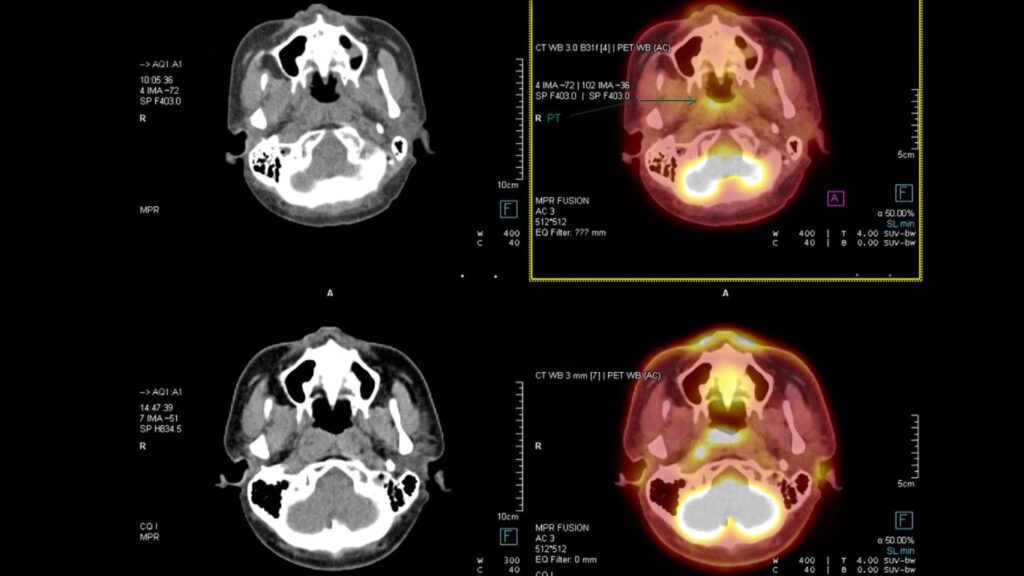

Tomografía para Detectar Cáncer: Precisión en Querétaro

En Altaria, entendemos la importancia de una detección temprana para el diagnóstico de cáncer. Nuestra tecnología de tomografía avanzada nos permite ofrecer un enfoque integral y preciso en la obtención de imágenes médicas. Sabemos que la salud de nuestros pacientes es primordial, por lo que garantizamos rapidez y confiabilidad en nuestros servicios de tomografía para […]

Tomografía y Resonancia: Servicios en Altaria, Querétaro

En Altaria, nos dedicamos a ofrecer un enfoque integral para el diagnóstico médico a través de nuestros servicios de tomografía y resonancia. Nuestro compromiso con la excelencia se refleja en la atención de calidad y en el uso de tecnología avanzada, lo que garantiza precisión y rapidez en la obtención de imágenes médicas. Desde nuestra […]

Tomografías Precisas y Rápidas en Querétaro

En Altaria, estamos comprometidos con ofrecer tomografías modernas y eficaces que facilitan diagnósticos médicos precisos y claros. Nuestras tomografías en Querétaro son reconocidas por su rapidez y calidad, permitiendo así a los profesionales de la salud tomar decisiones informadas que benefician a los pacientes. Al ser parte de un avance significativo en el ámbito de […]